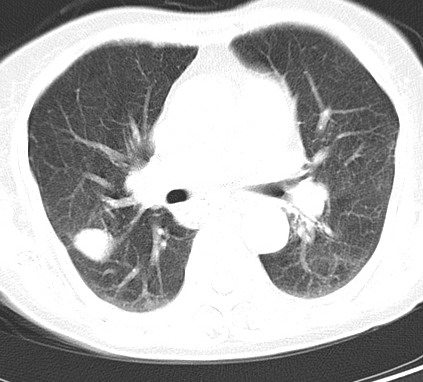

以下是引用hhcckk在2007-3-2 14:51:00的发言:[br]考虑结核球可能性大,依据[br]1病灶在下叶背段,结核的好发部位[br]2病灶内有大量的钙化,纵隔内有大量的淋巴结钙化[br]3重要的是半年前与现在相比无变化,假如是肿瘤的话不会这么‘善良’[br]4病灶周围卫星灶不明显,病灶有毛刺,胸膜凹陷,肿瘤不能完全排除,有条件的话最好做个活检

以下是引用liuyue在2007-3-2 17:15:00的发言:[br]1位置:右上叶后段[br]2性质:大分叶、粗长毛刺、条状斑片状钙化、纵隔多发淋巴结钙化,无强化,故考虑:肺结核灶(陈旧)